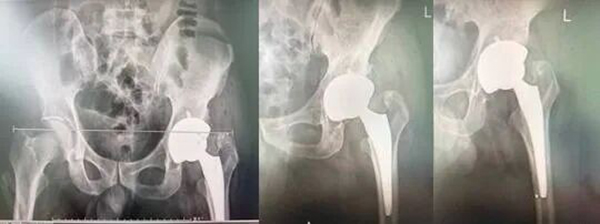

术后复查X线检查:

在完善各项术前准备后,由孙利副主任医师主刀,骨科团队为患者实施左侧全髋关节置换术。手术过程十分顺利,术中精准置入人工髋关节假体,同时严格校准下肢长度,成功将患者短缩的左腿恢复至与右腿等长,彻底解决了跛行隐患。

术后第5天:实现独立逐渐平稳行走,双下肢对称无明显跛行,关节活动度基本恢复正常。